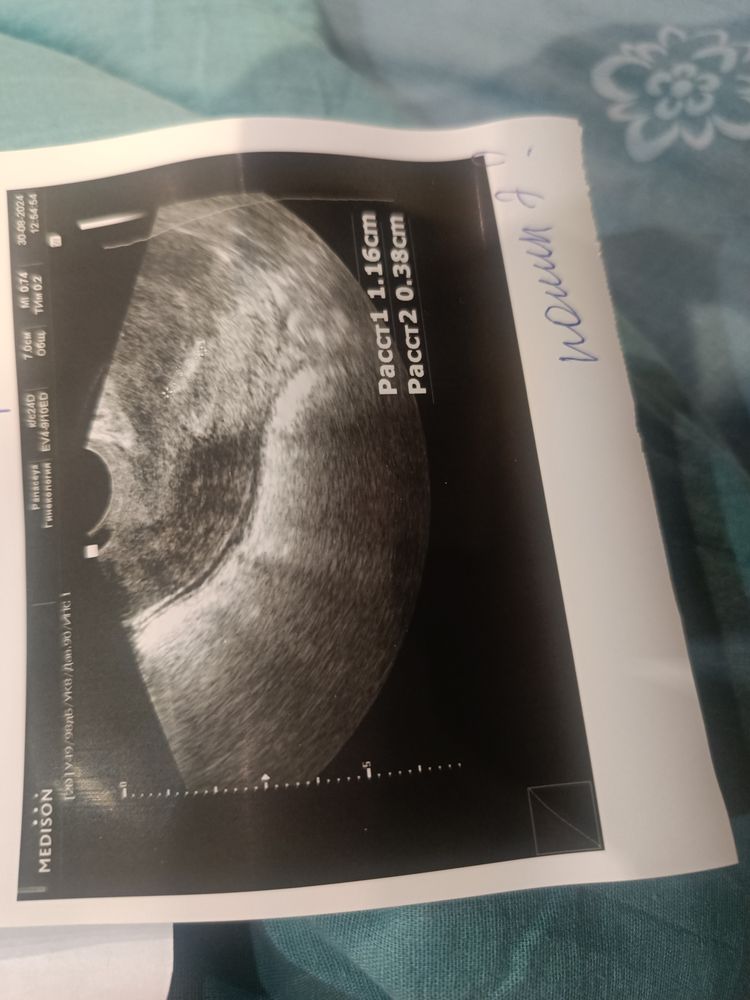

Девочки что такое анэхогенное включение?

Возможно полип всё таки

Так полип себя отражает , нужно идти на гистеру .

значит что-то пропускает через себя волны, а паутинка внутри эти же волны отражает. какие-то образования разной структуры, жидкость, сосуды, по клинической картине доктор посмотрит

Киста может быть